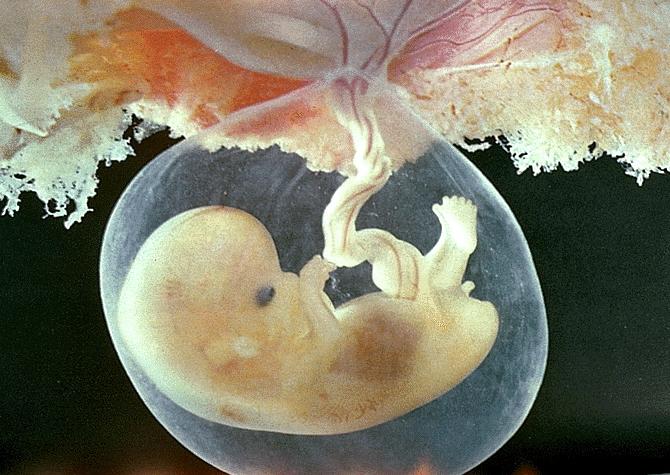

Удивительные фотографии эмбриона на 8 неделе беременности